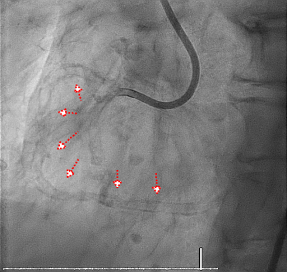

DSA示术前重度钙化影犹如支架术后